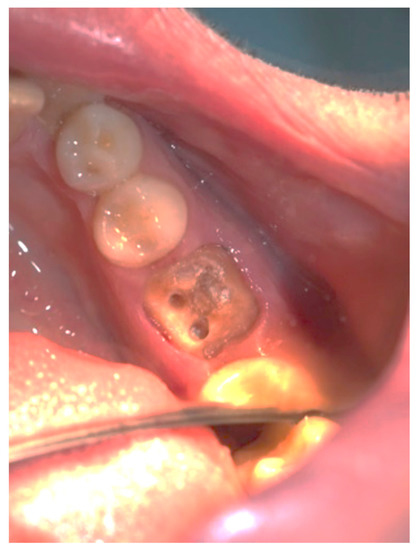

Figure 3, Figure 4, Figure 5, Figure 6, Figure 7 and Figure 8 display the follow-up of the healing process after a resective procedure for lengthening a short clinical crown with a laser.

Figure 3.

Soft tissue lengthening of a short clinical crown and subgingival finish line exposure of tooth 36: bleeding during the procedure was self-limiting, and the post and core impression was taken in the same visit.